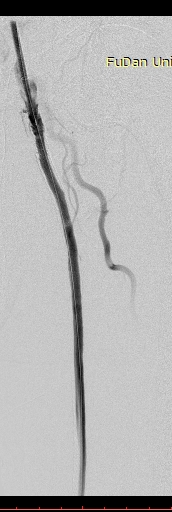

病例-1 男性,77岁,左下肢SFA支架术后7年,旁路术后3年静息痛 ABI:左侧 0.35